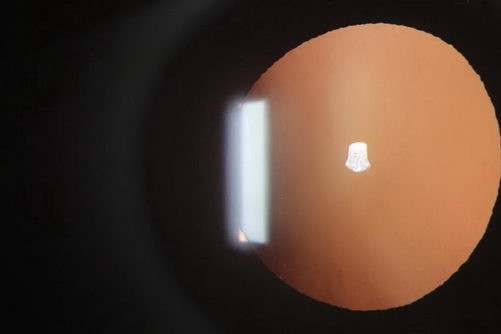

注:左图为李先生左眼的晶体前段照相

右图为正常的晶体前段照相

经检查,屈光手术中心肖迟主任告诉李先生,右眼视力0.15矫正0.8,左眼因晶状体浑浊明显,视力0.15只能矫正到0.3。不同于随着年龄增长而得的老年性白内障,这属于筋膜枪按摩眼球造成的外伤性白内障。